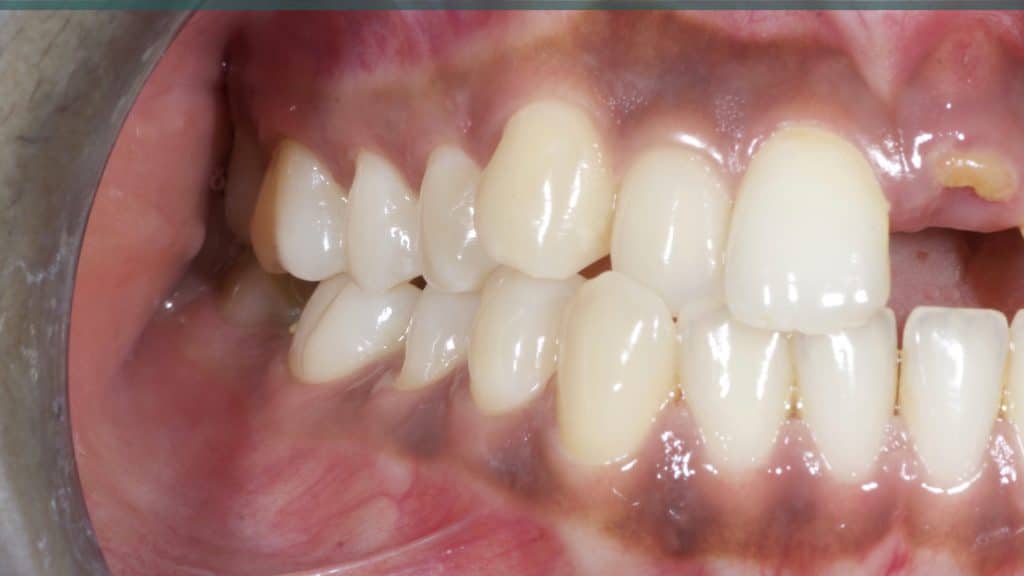

A 27-year female patient with dislodged Resin bonded FPD. She had that FPD for past few years, it had metal wings on palatal surfaces of UR1 and UL2 and a post like metal extension into the root canal of UL1. There was gingival abscess due to fractured root segment most probably due to extended metallic post like structure. Immediate implant placement (IIP) and Immediate restoration (IR) was planned for this patient.